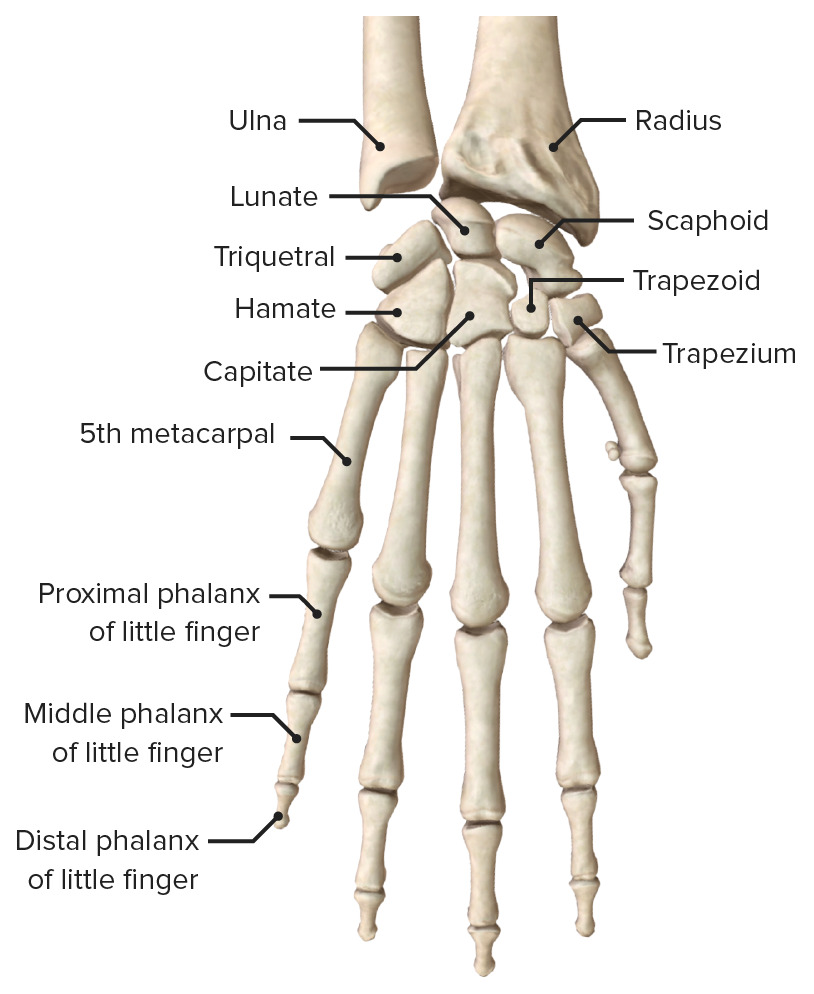

Las manos están formadas por más huesos y partes móviles que cualquier otra zona del cuerpo. Si están sanas, estas partes funcionan en conjunto. Realizan una gran cantidad de tareas. Las manos pueden hacer movimientos muy delicados. También pueden hacer tareas que requieren de mucha fuerza. Huesos.. Están localizadas en los extremos de los antebrazos, son prensiles y tienen cinco dedos cada una. A continuación os presentamos las 15 partes de la mano y sus funciones. 1. Los huesos de la mano. La mano humana está compuesta por un total de 27 huesos diferenciados en tres zonas en función de su posición.

Cada dedo tiene tres falanges (distal, media y proximal); solamente el pulgar tiene dos. Huesos metacarpianos. Los cinco huesos que componen la parte media de la mano. Huesos carpianos. Los ocho huesos que forman la muñeca. Los huesos carpianos están conectados a dos huesos del brazo–el hueso cúbito y el hueso radio.. falange: Uno de los huesos de los dígitos. Carpas de la mano izquierda: Hay ocho huesos carpianos en cada muñeca: escafoides, lunados, triquetrales, pisiformes, trapecios, trapecios, capitados y hamates. La mano contiene 27 huesos. Cada una pertenece a una de tres regiones: los carpos, (muñeca), los metacarpianos, (la palma) y las falanges.